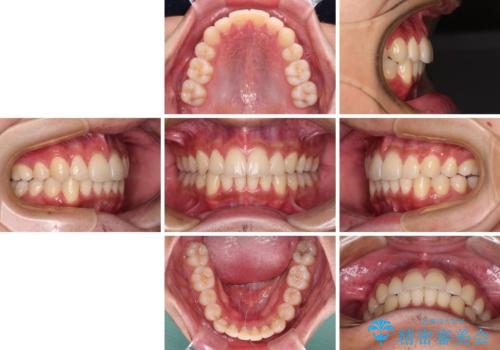

矯正治療の後戻りをインビザライン・ライトで解消

- 矯正治療の後戻りを気にして来院された患者様です。

後戻りは軽微であったので、インビザライン・ライトにより矯正治療を行うこととしました。

インビザライン・ライトは提供されるマウスピースの数に制限があり、通常のタイプよりもマウスピース提供期間が短くなっている一方、安価に治療を行うことができるプランです。

治療のゴールも変更できないため、軽微な歯列不正や、後戻り改善などに適しています。